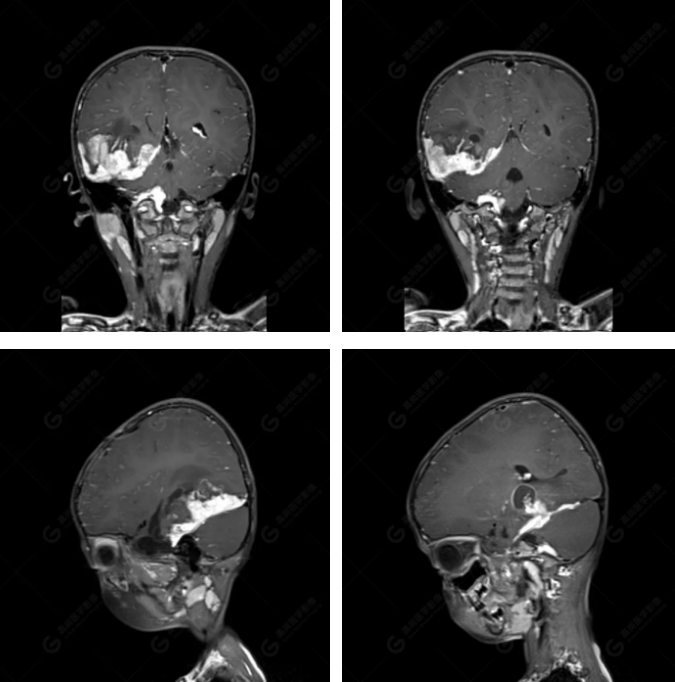

右側(cè)顳葉腫瘤切除術(shù)后(具體不詳):右側(cè)顳部骨質(zhì)不連續(xù)呈術(shù)后改變,右側(cè)顳葉術(shù)區(qū)見片狀長T1長T2信號影,F(xiàn)LAIR呈低信號;術(shù)區(qū)后方右側(cè)顳枕葉見一巨大占位性病變影,邊界欠清,大小約6.2×5.8×4.3cm(前后×左右×上下),信號不均勻,T1WI呈等稍低信號間雜少許高信號,T2WI呈高稍低混雜信號,DWI示部分病灶彌散受限,相應(yīng)ADC圖減低,磁敏感序列見部分呈極低信號,增強掃描可見明顯不均勻強化,鄰近硬腦膜及小腦幕增厚并明顯強化;另延髓右前方及右側(cè)橋小腦角區(qū)見一不規(guī)則形異常信號影,大小約3.2×1.3×3.7cm(左右×前后×上下),呈長T1稍長T2信號,F(xiàn)LAIR呈等信號,DWI未見受限,增強后明顯均勻強化,鄰近腦膜明顯強化。鄰近腦實質(zhì)及右側(cè)顳角明顯受壓;左側(cè)大腦半球未見局灶性信號異常,中線結(jié)構(gòu)稍左移。

右側(cè)顳葉腫瘤切除術(shù)后:現(xiàn)術(shù)區(qū)后方右側(cè)顳枕葉及延髓右前方占位,右側(cè)顳枕部硬腦膜及小腦幕明顯強化,結(jié)合既往影像資料,考慮為胚胎源性惡性腫瘤,如非典型畸胎樣/橫紋肌樣瘤(AT/RT)或原始神經(jīng)外胚層腫瘤(PNET)。

術(shù)后隨訪病理結(jié)果:非典型畸胎樣/橫紋肌樣瘤。